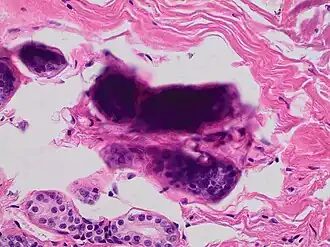

Stacking of cells on top of each other gives a dark look, and in this breast tissue it may mimic microcalcifications. -

Pap stained smear of a monocyte with nuclear smearing or smudging artifact, seen as a tail-like extension of nuclear material -

Small cell carcinoma is a cancer where the presence of smudging is a clue to the diagnosis.[6]